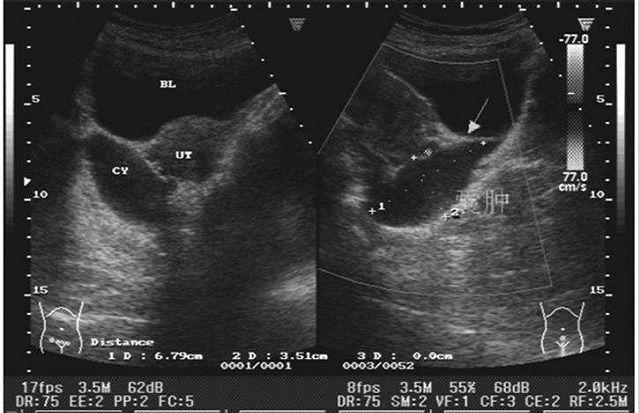

卵巢的一些囊肿是可以做穿刺的,特别是一些比较大的,单纯型的囊肿,一般靠近腹壁或者靠近阴道后穹窿就可以做一些穿刺,穿刺的部位就可以通过腹壁穿刺,也可以通过阴道后穹窿穿刺。

但是在穿刺的过程中还是需要有B超监测的,在B超下面穿刺相对安全一些,因为在肚子里面。